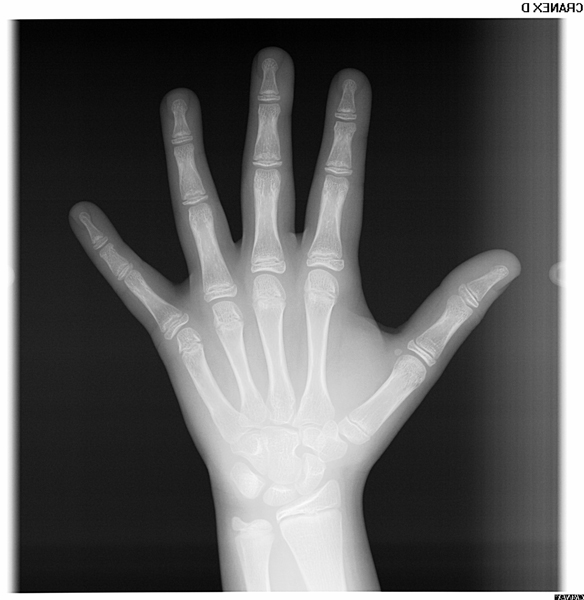

Radiografia de Mão e Punho